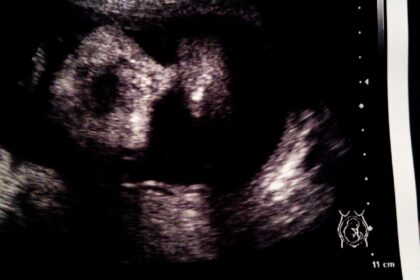

昨日の検診で、

「予定日も過ぎたので、そろそろ入院時期とかも相談しましょうか」

と言われ、まだそういう話は出ないと思っていたのでびっくり。

とりあえず、来週月曜日に検診を受けることにして

その時点で産まれていなかったら、入院時期を決めることになりました。